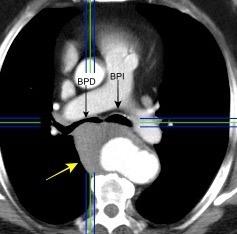

53. BPI .COMPRESIÓN Y DESPLAZAMIENTO HACIA ARRIBA DEL

55. BPI . COMPRESIÓN Y DESPLAZAMIENTO HACIA ABAJO DEL

Densidad baja uniforme del espacio. Pared interna de BPI-BI visible.

BPI sin alteraciones Ángulo carinal normal

Crecimiento AI

Ganglios Quiste broncogénico